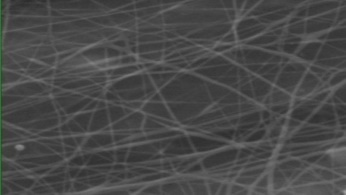

Morphology, size and size distribution of the nanofibres

Morphology analysis was adapted from Aytac et al. (2019) [38]. The SEM analysis was conducted to detect electrospun nanofibers' fibre shape and diameter. The electrospun nanofibres from 18 runs were investigated individually by SEM (FEI, quanta 450, Czech). Images revealed the morphology of resultant nanofibers and measured their diameters in nanometres. The average number of records was calculated using a standard deviation estimation. The setting of the SEM machine was conducted on voltage 25.00 kv, magnification 23624 and width (8.3-9.3 mm).

Results of the SEM analysis are listed in table 2, with a wide range of fibre diameters starting from 87.2 nm (run 13) to 2500 nm (run 18). Run 18 did not produce true nanofibers due to the deficient concentration of PVA. The statistical analysis revealed that the effect of each polymer (factor) on the diameter size of the electrospun nanofiber was vast. Therefore, there is a correlation between factors A, B and C and fibre diameter as expressed in equation 5.

Fig. 3: Nanofibres SEM images with nanofiber diameter frequencies. The PVA, PEO and HPMC were symbolised as V, E and P. Data are given in mean±SD, n=3

The morphology of nanofibers would be affected by device parameters such as flow rate, voltage and distance from the collector. Also, nanofibres' properties could be changed due to temperature and humidity. The bead formation appears with a low concentration of PVA (run 2) or a high concentration of PEO and HPMC (runs 6 and 11), as shown in fig. 3. Therefore, increasing PVA concentration leads to beads' disappearance and smooth fibres' formation. Nageeb El-Helaly (2021) and Silva J. A. et al. (2021) reported similar results [47, 48]. Kalluriet al.(2021)[49] studied the relationship between the fibre diameter, bead diameter and flow rate. Thus, they concluded that better fibre uniformity and bead formation were needed at a high flow rate. These results appear clearly in run two and run six and agree with Silva et al.(2021) results [50], who reported that only the concentration of PVA (≥ 15%) could produce uniform nanofibers when using the lower molecular weight of PVA (67,000). Fibre diameter of 15% PVA and more appeared to be in the range 87.11 to 252.5 nm with uniform fibres and disappearance of beads except in run 6, where the beads appear due to increasing the concentration of HPMC as highlighted by Gripet al. (2018) [46].